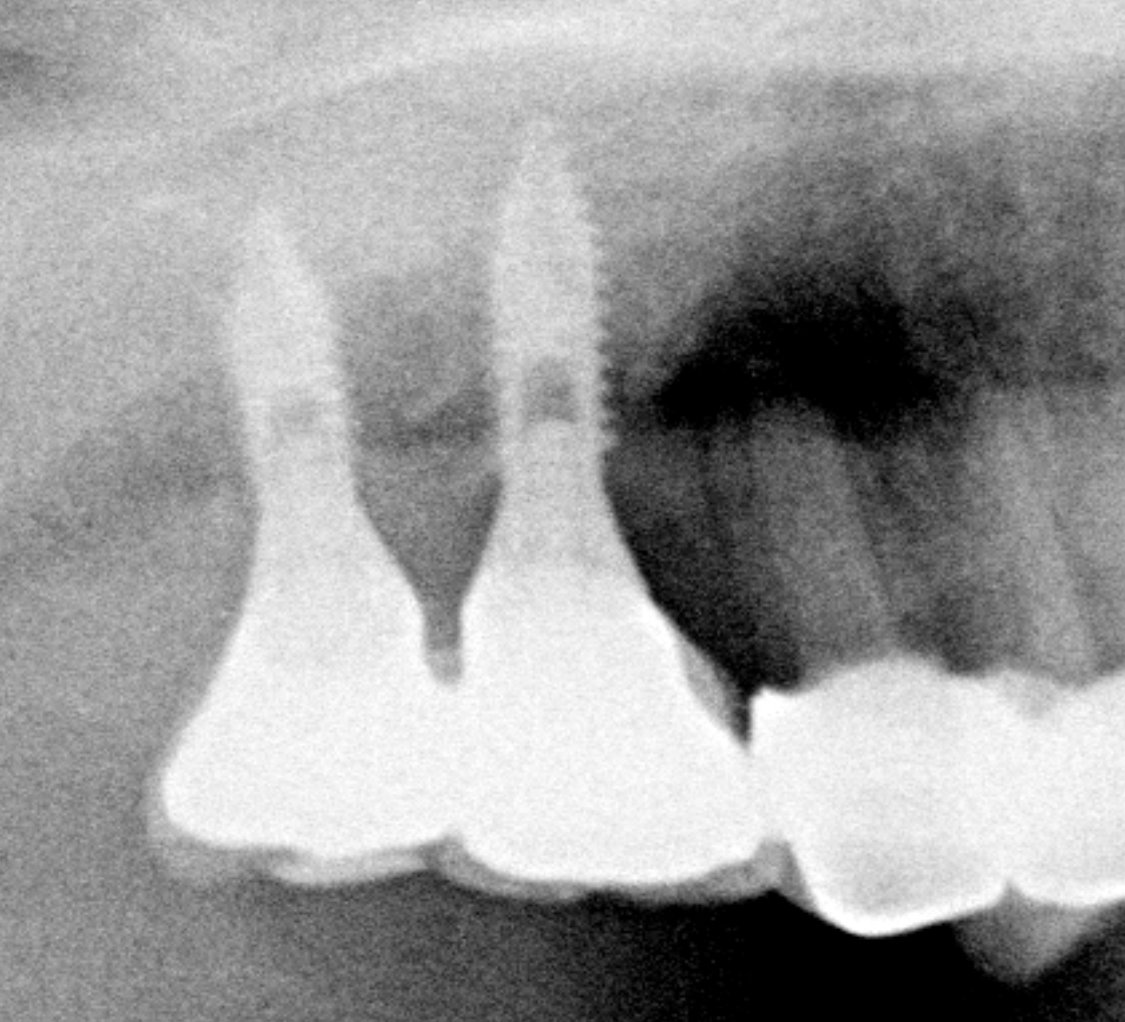

Los implantes de la zona anterosuperior, son implantes de conexión interna y tienen las coronas atornilladas directamente al implante sin pilar intermedio. Son implantes que se hizo hace unos 12 [...]